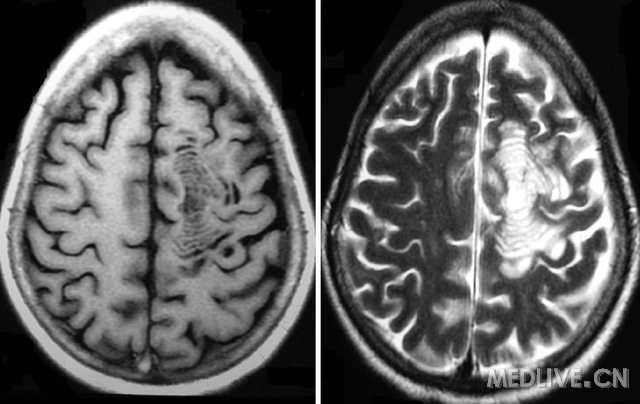

为什么 Balo 病变发展称片状或同心圆状?病变似乎是因为对未知刺激的反应之后在血管周围区域产生的,导致巨噬细胞和激活的小胶质细胞产生细胞因子,氧自由基或其他神经介质,诱导脱髓鞘形成。这种同心圆形的模式代表着化学介质从核心区像波浪一样像外传播 ( 图 4)

4. Balo 病变形成的假设模型

损伤可能是由于缺血缺氧所致,可能的机制包括线粒体呼吸链复合体 IV 及其催化组件细胞色素 C 氧化酶受抑制。当病灶形成时在其周围发现低氧诱导因子,D – 110,缺氧诱导因子 1α和热休克蛋白 70 等,这在一定程度上发挥了神经保护作用,使得在环状的脱髓鞘之间有部分髓鞘得以保留。数学模型表明,同心性分层中还有可能是由于非线性的单核细胞趋化和小神经胶质细胞对非特异性化学诱导物反应,导致在这些细胞聚集的区域脱髓鞘。

髓鞘脱失也可能与星型胶质细胞病变有关。连接素形成星形胶质细胞之间以及其与少突胶质细胞之间缝隙连接。在扩大的 Balo 病变的前缘,星形胶质细胞水通道蛋白 4 和连接素 ( 如 Cx43) 明显减少,并且与少突胶质细胞和髓鞘密切相关。这个观察表明,星形胶质细胞和少突细胞相互作用的破坏导致脱髓鞘。相关补体,免疫球蛋白沉积或抗水通道蛋白 4 抗体的缺乏使得该病的免疫病理学与视神经脊髓炎截然不同。